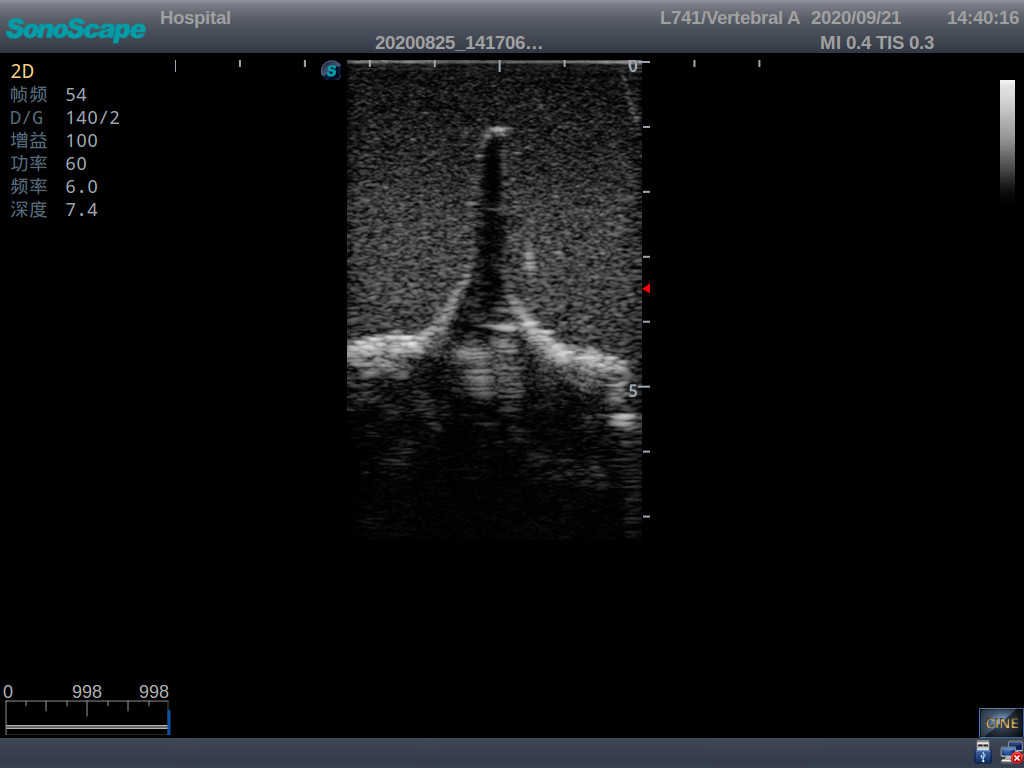

Adult Lumbar Puncture Ultrasound Training Model

This model is an ideal choice for ultrasound-guided adult lumbar puncture training with true-to-life skin feel and touch, accurate anatomical structures as well as real clinical ultrasound images. Realistic resistance to needle tips and correct landmarks provide excellent hands-on experience.

Accurate anatomical structure of L1-L5 and the vertebral canal

2)  Real clinical ultrasound images

3)  Compatible with various real ultrasound machines

1)   Ultrasound-guided lumbar puncture practice